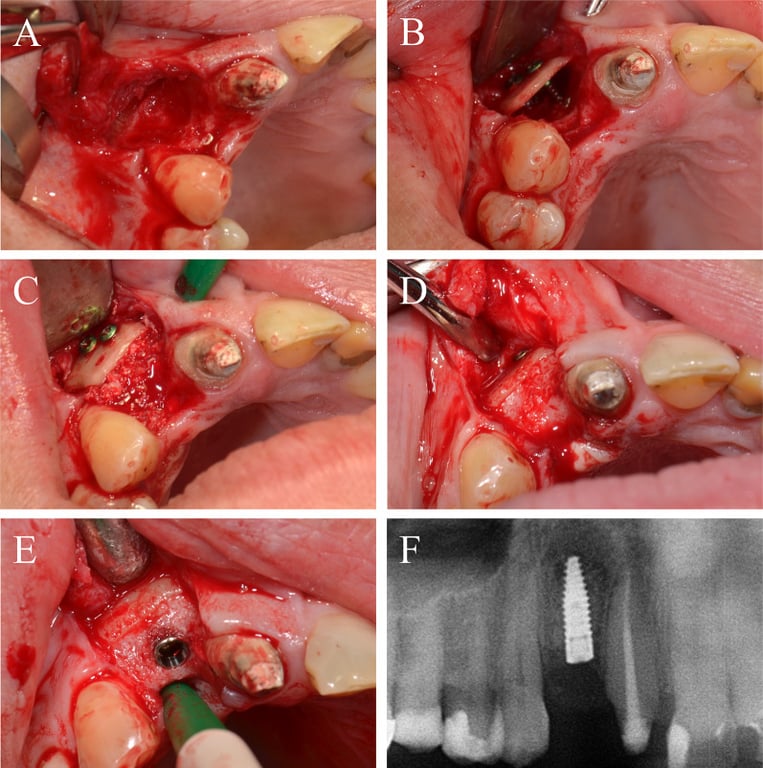

Fig. 5.

Alveolar ridge augmentation of the anterior maxilla. A Initial intraoperative situation demonstrating an extended tub-shaped alveolar defect after a failed augmentation attempt using an autogenous graft from the mandibular angle and postoperative hypesthesia of the mandibular nerve. B An allogeneic cortical bone plate was placed and fixed by adjusting screws. C The occurred space was filled with allogeneic spongious granules. D Four months later, a sufficient bone bed was found and E a bone level tapered implant was inserted. F X-ray demonstrating the inserted implant